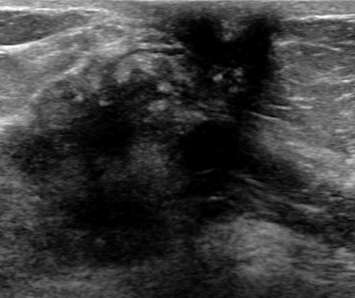

The ultrasound above demonstrates a well-circumscribed, anechoic, parallel, and avascular tubular structure with well-defined borders, consistent with a dilated duct. The opposite breast also revealed similar dilation of the ducts, this symmetry is reassuring and benign. Features of ductal dilation which are concerning (and may warrant biopsy) include unilateral breast ductal dilation or a focal ductal dilation in a breast with otherwise normal sized ducts. Furthermore, a dilated duct which is not anechoic (fluid filled or with internal soft tissue nodularity), with an irregular shape, or with indistinct margins are also more suspicious.